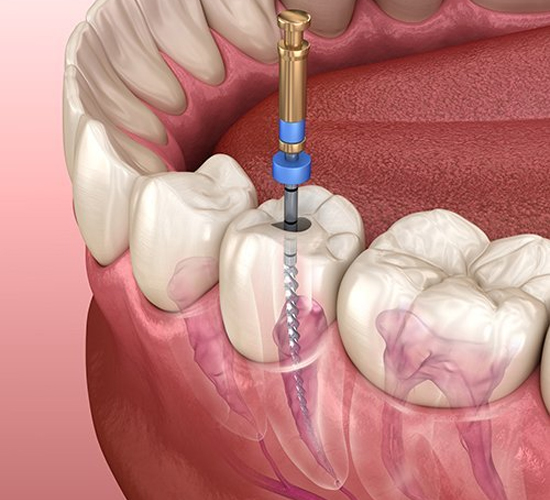

Root canal is a treatment to repair and save a badly damaged or infected tooth instead of removing it. The term "root canal" comes from cleaning of the canals inside a tooth's root.

Beneath the white enamel or your teeth and the dentin layer, there is soft tissue called the pulp.